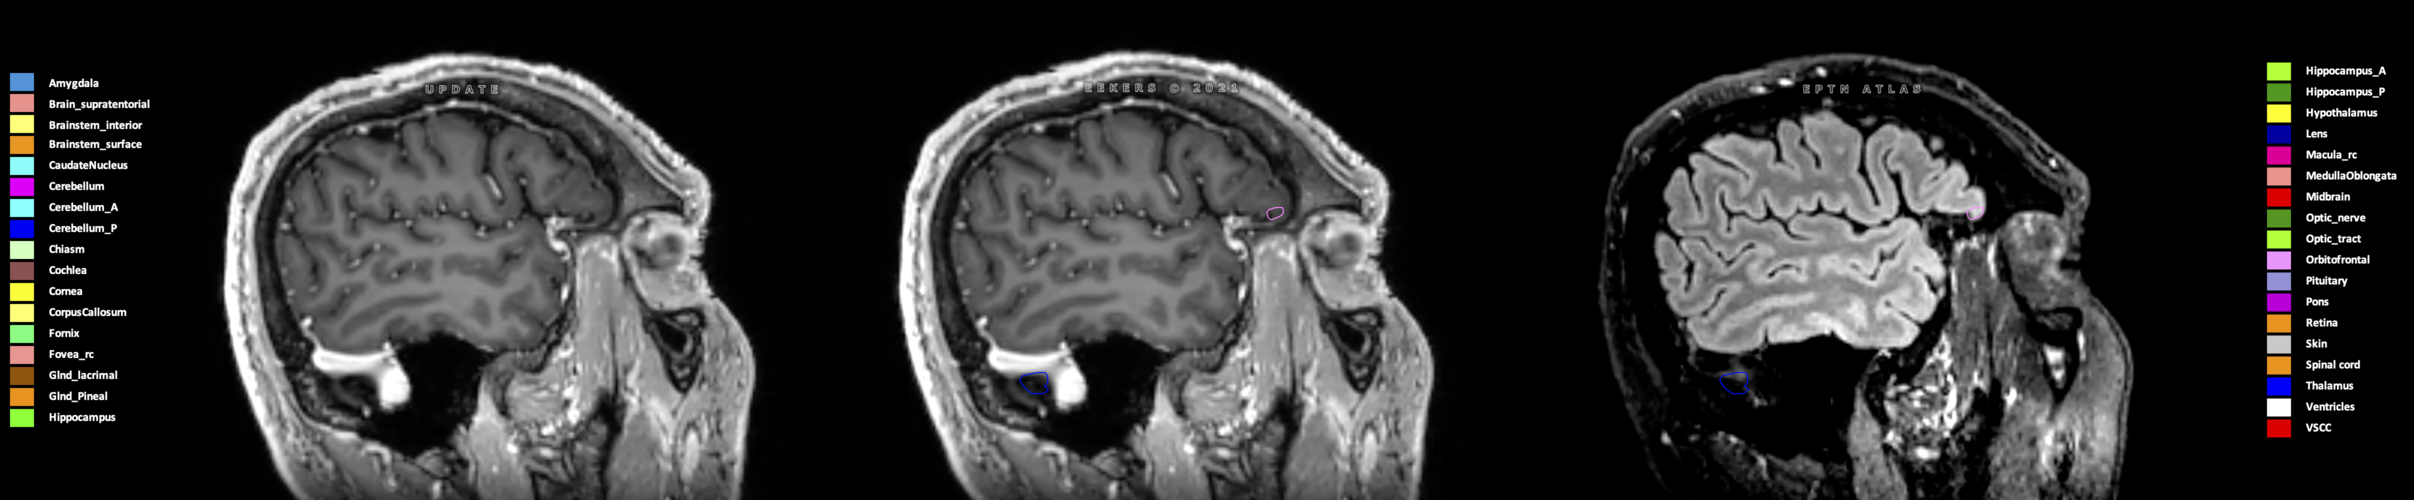

Eekers et al. have published an international neurological atlas for contouring of organs at risk in consensus with the European Particle Therapy Network (EPTN) in 2018 and an update in 2021. The purpose of this consensus atlas is to decrease inter- and intra-observer variability in delineating OARs relevant for neuro-oncology.

Included are all OARs known to be relevant for radiation-induced toxicity in neuro-oncology: brain, brainstem (midbrain, pons, medulla oblongata), chiasm, cerebellum (anterior & posterior), cochlea, cornea, hippocampus (anterior & posterior), hypothalamus, lens, lacrimal gland, optic nerve, pituitary, skin, and vestibular & semicircular canals. To further facilitate research on cognition, vision and radiological changes after irradiation of the brain, potential clinically-relevant OARs are included: amygdala, caudate nucleus, cerebellum (anterior & posterior), corpus callosum, fornix, macula, optic tract, orbitofrontal cortex, periventricular space (PVS), pineal gland, and thalamus.

Three-dimensional delineation of the 25 consensus OARs for neuro-oncology are shown on CT (WW/WL 120/40, 3000/600), 3T MR images, (T1Gd, T2FLAIR 1mm) and 7T MR (MP2RAGE 0.7 mm). All are presented in transversal, sagittal and coronal view.